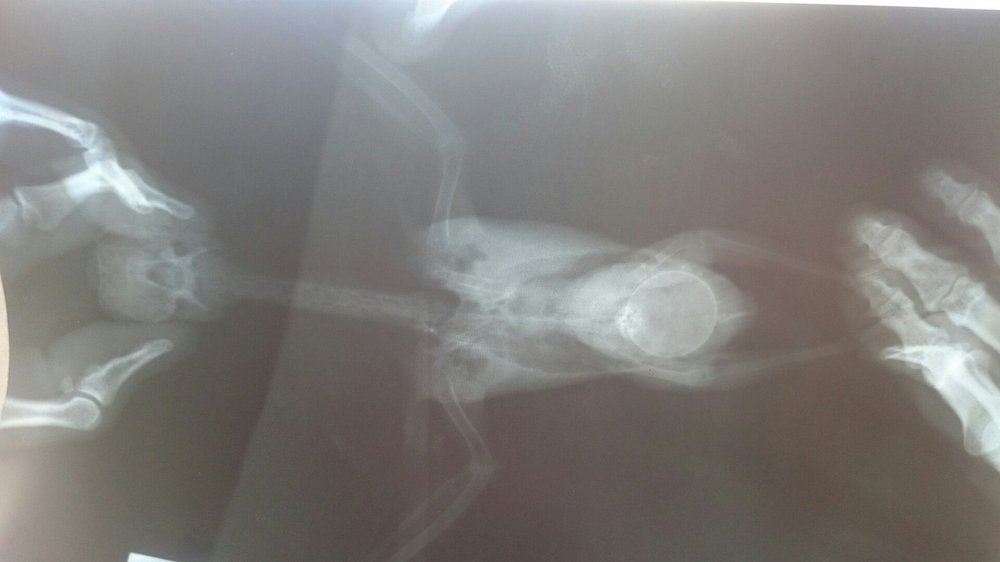

Вчера ездили в Симферополь, нам сделали рентген и анализы , сказали, что восполение клоаки, возможно храническое, и по почкам тоже что-то не очень в порядке, но анализ крови у таких мал. птичек не берут, прописали лечение) На подходе видно 3 яйцо, к-рое вчера было благополучно снесно на двери:bird:Надеюсь, лечение поможет